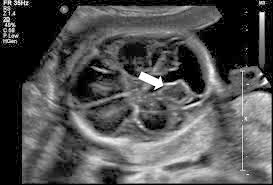

Thùy nhộng tiểu não thai nhi là gì? Chính là phần mô tiểu não nằm ở đường giữa, nối hai bán cầu tiểu não. Trên siêu âm, cấu trúc này thuộc vùng hố sau, nằm phía sau thân não và liên quan chặt với não thất IV. Williams Obstetrics mô tả ở mặt cắt xuyên tiểu não có thể thấy hai bán cầu tiểu não. Thùy nhộng và não thất IV nằm phía trước thùy nhộng.

Ở siêu âm hình thái thường quy, bác sĩ sẽ khảo sát mặt cắt xuyên tiểu não để nhìn tiểu não và bể lớn. Theo Williams, bể lớn trong tam cá nguyệt hai thường đo từ 2 đến 10 mm. Nếu lớn hơn, cần nghĩ đến các chẩn đoán phân biệt như bất thường thùy nhộng, nang hố sau hoặc mega cisterna magna.

Mặt cắt đứng dọc giữa quan trọng ra sao

Đây là mặt cắt then chốt để nhìn rõ thùy nhộng, não thất IV, thân não và lều tiểu não. ISUOG xem mặt cắt này là phần rất quan trọng của khảo sát thần kinh thai chuyên sâu. Tài liệu chuyên ngành cũng cho thấy việc đánh giá hình dạng não thất IV. Góc giữa thân não và thùy nhộng, cũng như mức nâng của lều tiểu não giúp phân biệt các nhóm bất thường hố sau.